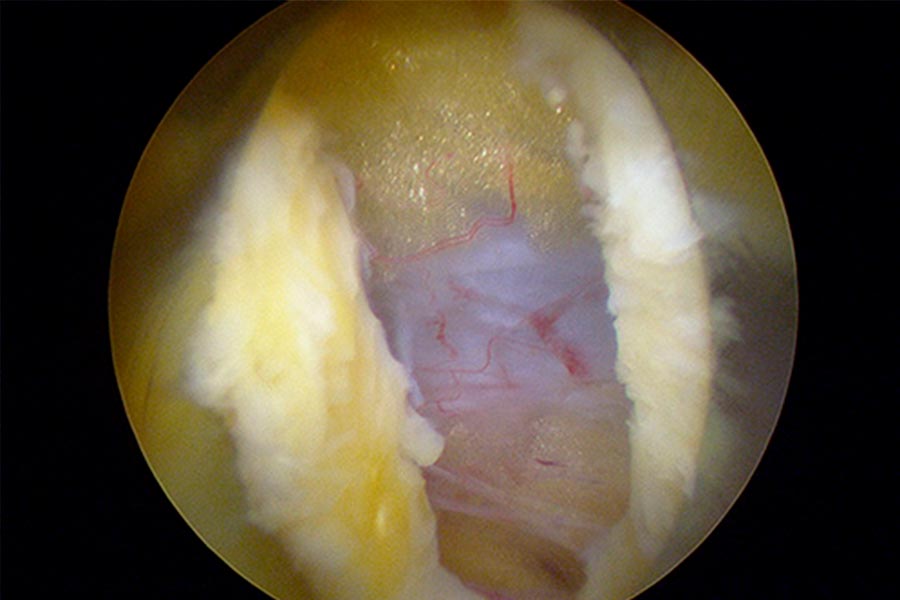

Caso clínico: endoscopia de columna multinivel L4L5 y L5S1

Durante la intervención quirúrgica, se abordarán los dos niveles mediante la técnica de endoscopia de columna.